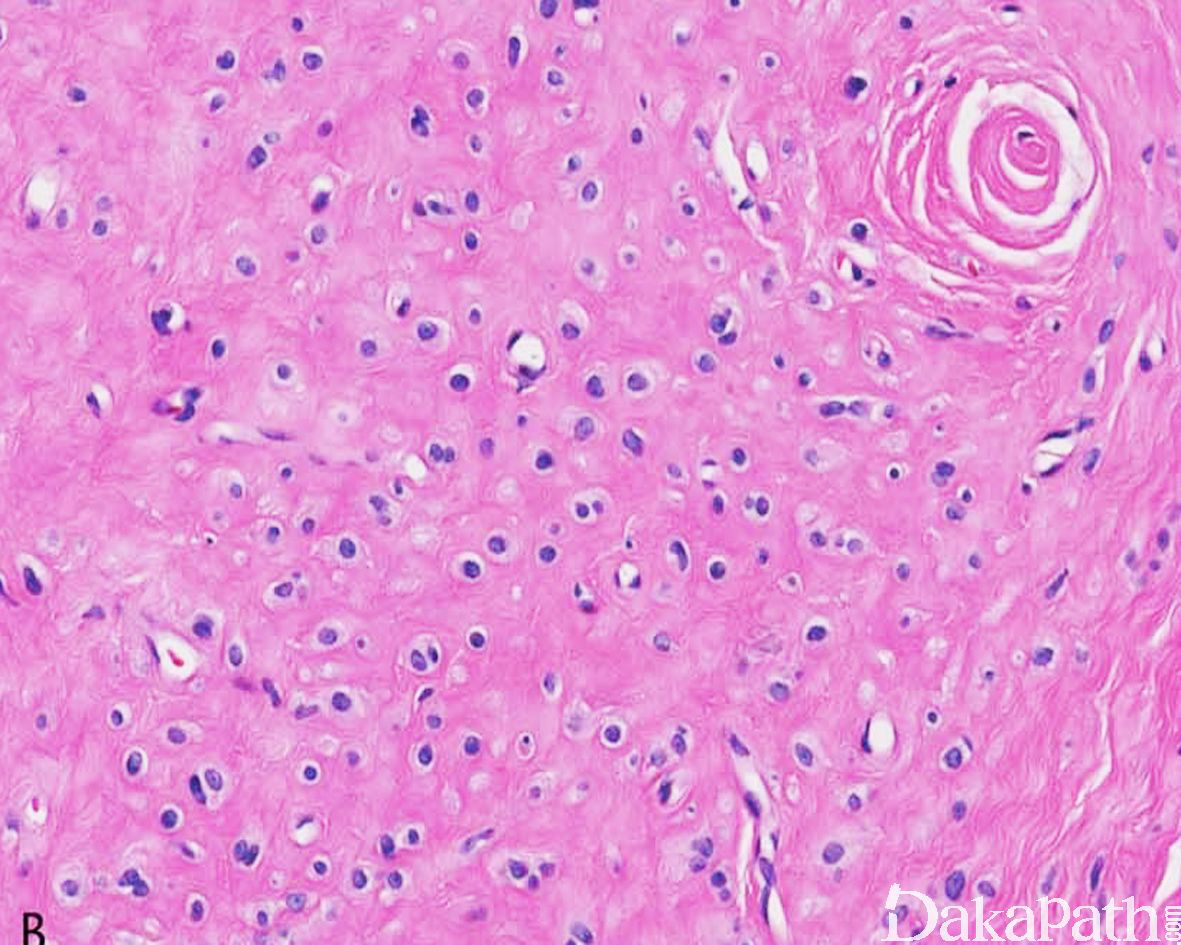

瘤细胞呈梭形至圆形,呈索状、梁状和链状排列;

间质大量纤维组织增生、硬化;

瘤细胞无异型性,无核分裂象。